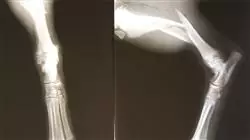

La connaissance de la pathologie de Genou chez l'adolescent est cruciale pour la survie de la hanche à l'âge adulte. Un diagnostic tardif de l'épiphysiolyse des genoux, par exemple, peut entraîner une perte de la fonction de la hanche et la nécessité d'une prothèse totale de celle-ci à un âge anormalement précoce. C'est pourquoi ce programme vous apprendra à la diagnostiquer précocement et à la gérer correctement, y compris par des interventions chirurgicales complexes de réduction.

1.8. Épiphysiolyse des fractures du fémur distal et du tibia proximal

1.8.2. Diagnostic

1.8.3. Traitement